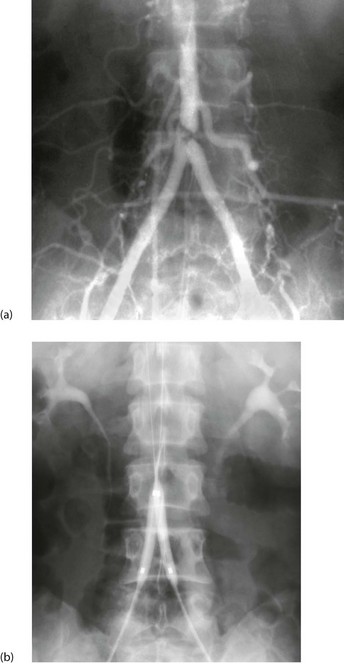

Fig. 5.7 Percutaneous transluminal angioplasty

This man of 55 presented with bilateral calf and thigh claudication. (a) A localised severe stenosis of the distal abdominal aorta. (b) The ‘kissing balloon’ technique used to dilate the stenosis. Two balloons, shown inflated, are used to prevent asymmetrical dilatation which might compromise the opposite common iliac artery